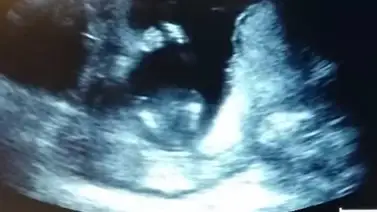

Una mujer embarazada de 14 semanas acudió al médico junto a su marido para hacerse una ecografía. El médico comienza a pasarle el ecógrafo por la barriga a la futura madre, y ésta se encuentra a su bebé dando palmas.

Los padres comienzan a cantar ‘If You’re Happy and You Know it Clap Your Hands’: ‘Si eres feliz y lo sabes, da las palmadas’. Y el bebé les sigue el ritmo, al menos eso parece.

“Es una experiencia que nunca olvidaré. El bebé dio las palmas tres veces, entonces el doctor volvió sobre él mientras sus padres le cantábamos. No hay más misterio. Es impresionante”, escribió la madre en su canal de YouTube, Jen Cardenal.